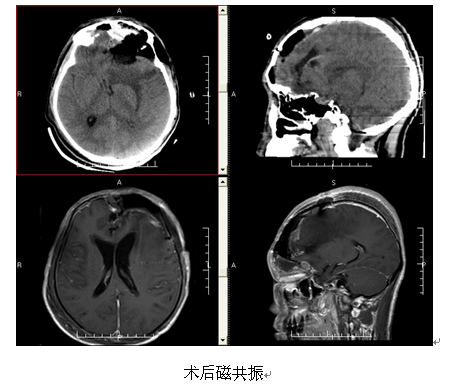

治疗:入院后查头颅MRI平扫+增强,CTA示:1.左侧额部巨大占位性病变,并跨额骨突向颅外,向前下突入左侧额窦与筛窦内,考虑脑膜瘤可能性大;2.左侧大脑镰下疝及左侧海马钩回疝。向家属交代病情,诊断明确,有手术指征,告知术中术后相关风险后,家属表示理解并同意手术治疗。先行肿瘤栓塞术,术后送手术室行左侧额部颅内外沟通肿瘤切除,术中可见肿瘤位于左侧额部,侵犯并突破额骨,并突破颅底,进入额窦以及筛窦,肿瘤血供丰富,边界清楚,质韧,镜下予分块全切除肿瘤,术程顺利,术后予部分颞肌及脑膜补片重建颅底,术后予止血、抗感染、神经营养及补液等治疗,术后复查头颅CT、MRI示:呈术后改变,肿瘤全切除。

病理结果:脑膜瘤 WHO II级。

出院情况:患者一般情况可,裸眼视力:左眼视力4.5,右眼视力4.4,佩戴眼镜后左眼视力4.9,右眼视力5.0。